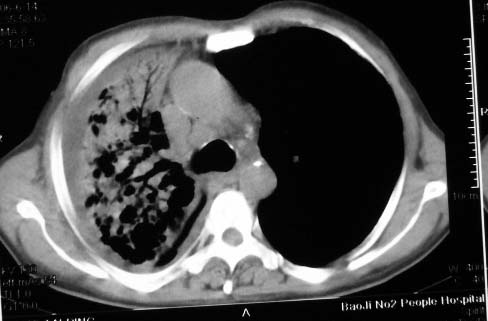

影象表现:右肺上叶大片状、网格状及索条致密影,蜂窝影,其内参杂斑点状小结节,密度不均匀,内见含气支气管像,纵隔内见肿大淋巴结.

抗感染病变无明显改善,右上叶大片状增弥不均匀病灶,夹杂网状及支气管充气像,肺门纵隔淋巴结肿大,右侧胸腔积液。考虑1混合感染伴肺间质改变[警惕特殊感染,如真菌]。2细支气管肺泡癌。建议结合临床及进一步检查[如痰,胸水脱落细胞检查及支气管镜检灌洗或穿刺活检

影象表现:右肺上叶大片状、网格状及索条致密影,蜂窝影,其内参杂斑点状小结节,密度不均匀,内见枯枝样含气支气管像,纵隔内见肿大淋巴结.胸膜广泛增厚,前胸壁似受累.少量胸腔积液.纵隔内淋巴结的直径>1.5cm.右侧胸廓体积缩小.考虑:1 肺结核合并间质纤维化 2 细支气管肺泡癌

右肺上叶大片状、网格状及索条致密影,蜂窝影,其内参杂斑点状小结节,密度不均匀,内见枯枝样含气支气管像,纵隔内见肿大淋巴结.胸膜广泛增厚,前胸壁受累增厚.少量胸腔积液.纵隔内淋巴结的直径>1.5cm.右侧胸廓体积缩小.考虑: 细支气管肺泡癌并肺内癌性淋巴管炎。